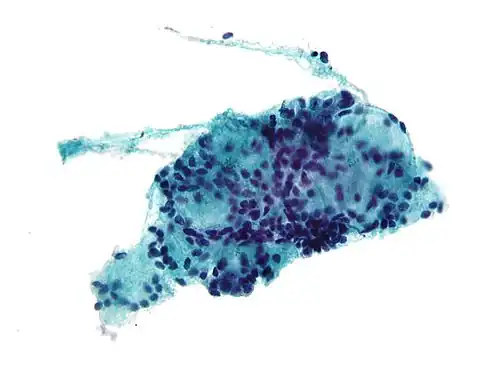

Biopt van adenoïdcystisch carcinoom, aspiratiemonster met fijne naald -